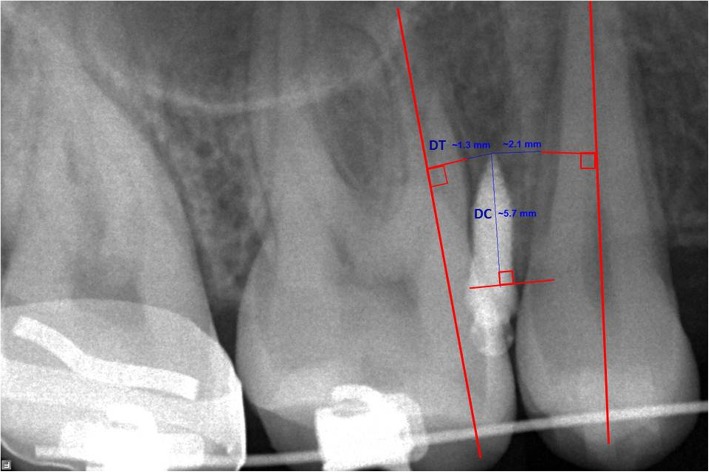

The radiographs were processed using the manufacturer’s program (Cliniview Software, Version 9.3.0.6); their ratios to actual size were 1:1. The following measurements were recorded (Fig.1):

Perpendicular distance from the MI tip to the root of the most adjacent tooth (DT); the perpendicular was projected to the long axis of the adjacent root.

Perpendicular distance from the MI tip to the alveolar crestal bone level (DC); the perpendicular was projected to the tangent to the alveolar crestal tip. The shortest distance to either the mesial or distal root was considered in the statistical computations.

Fig. 1.

Radiographic evaluation using a periapical radiograph